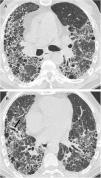

Reticulonodular infiltrates are seen on chest radiographs, and as they progress, ground-glass opacities and consolidations may appear. The main findings on CT are ground-glass opacities, centrilobular nodules and air cysts, which are present in up to 80% of cases (Fig. 10). Subpleural nodules, septal and peribronchovascular thickening, and lymphadenopathy may also be seen. Air cysts are few in number, usually less than 3cm, are frequently seen in ground-glass areas, and are random in distribution, although they are often seen adjacent to a vessel or bronchus and can also be subpleural.44,45 On follow-up CT, nodules and ground-glass opacities may disappear, but cysts may persist.46 Partial airway obstruction secondary to peribronchiolar lymphocytic infiltration with distal air trapping has been hypothesised as a pathogenic mechanism of these cysts. There may also be ischaemia due to vascular obstruction.9,11,40,43–45 Identification of these cysts is useful for the differential diagnosis with cellular NSIP and lymphoma, but can be difficult both with CT and pathology.40,42,43,47 In patients with LIP associated with Sjögren’s disease, the appearance of large nodules should lead to suspicion of amyloidosis—especially if the nodules are calcified—or lymphoma.10,40 (Fig. 11) On CT, hypersensitivity pneumonitis can present very similar findings to those of LIP, with cysts in up to 13% of cases.8 Differentiation can also be difficult for the pathologist, but usually the clinical context helps with the differential diagnosis.

Lymphoid interstitial pneumonia (LIP) in a 65-year-old woman with Sjögren's syndrome. (A) The HRCT image at the level of the pulmonary hila demonstrates multiple thin-walled air-filled cystic images. Also note the presence of ground glass opacities (arrow). (B) The image reconstruction in the coronal plane reveals the diffuse distribution of the findings.